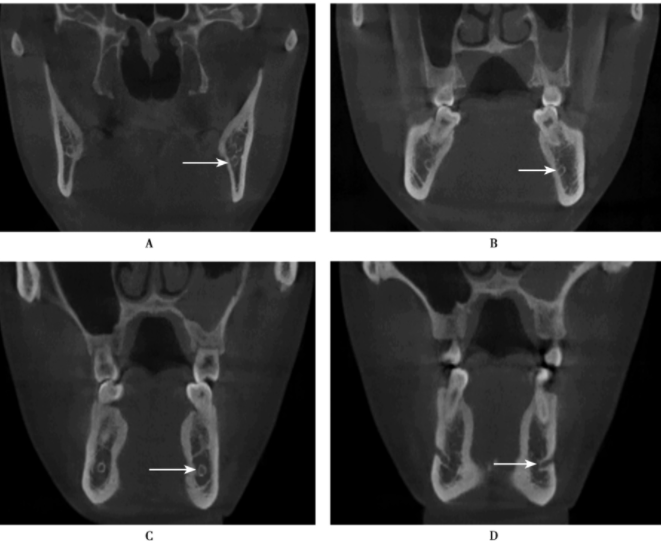

图6 CBCT冠状位

CBCT冠状位图像(A~D)显示下牙槽神经管从下颌体从后向前走行,在后段靠近舌侧骨皮质,往前行时逐渐靠近颊侧,最后开口于颏孔